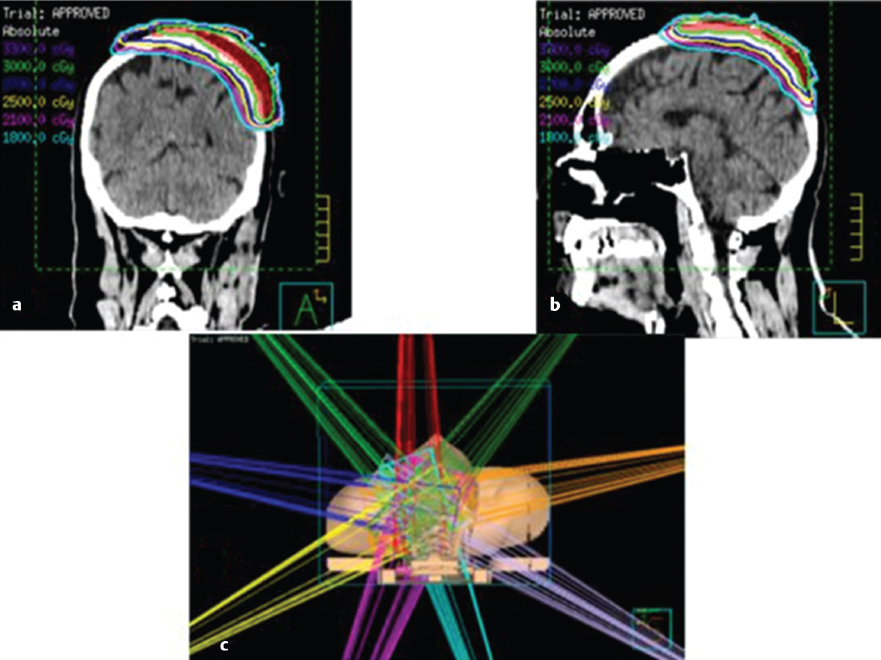

7 Role of Radiotherapy in the Treatment of Skin Malignancies Non-melanomatous skin cancers (NMSC), specifically basal cell carcinoma (BCC) and squamous cell carcinoma (SCC), are the most common malignancies in the United States. They are primarily managed surgically and carry an excellent prognosis, with a 1 to 5% rate of disease recurrence after complete excision and only exceedingly rare instances of distant metastasis. Historically, radiotherapy played a prominent role in the definitive management of these cancers as an alternative to surgical resection, especially in cosmetically sensitive areas. With the improvement in surgical techniques in recent decades, especially the widespread use of Mohs micrographic surgery (MMS), the use of curative radiation for skin cancers has declined. However, radiation is still commonly used in the definitive setting for patients with NMSC who are poor surgical candidates or have larger lesions in cosmetically sensitive regions of the face, and in the postoperative setting for more advanced tumors that have high-risk pathologic features that are associated with excessive risks of locoregional recurrence after surgery alone. Radiotherapy plays a similar role in the postoperative management of cutaneous melanoma. Radiation also offers excellent palliation for noncurable patients. This chapter reviews common indications, dose and fractionation schedules, techniques, and oncologic and cosmetic outcomes for radiotherapy for NMSC and melanoma ( Both surgery and RT can offer excellent cure rates for the management of early-stage NMSC. Surgery is typically the preferred method of treatment, given it can be performed in a single session, and has been associated with superior oncologic and cosmetic outcomes. One prospective randomized study compared the outcomes of MMS and definitive RT in 347 patients with less than 4 cm BCC of the face. The local failure rate was 0.7% for patients treated with MMS and 7.5% for patients treated with RT. Additionally, the cosmetic outcome was rated “good” or better more often in those patients who underwent surgery (87 vs. 69%).1 Though the technique of RT was not controlled (55% received interstitial brachytherapy and 45% received orthovoltage therapy), which could have affected the quality of the comparison, as the only randomized study, this trial remains pivotal in guiding medical decision making. A variety of factors can influence the decision to favor RT rather than surgery for NMSC. Typical contraindications to definitive RT include very large tumors and those with bone and/or cartilage invasion, given that control rates are typically inferior, as well as recurrent tumors that have been previously radiated or arise in an area of previous radiotherapy. Radiation should also be avoided in patients with genetic radiosensitivity syndromes, such as xeroderma pigmentosum and basal cell nevus syndrome, and in those with active connective tissue diseases, such as scleroderma and systemic lupus erythematosus.2 Patients who are candidates for definitive RT include those with unresectable disease, older patients with comorbidities limiting their surgical options, and patients with lesions involving the eyelid, canthi of the eye (especially those who carry surgical risk to the lacrimal duct), external ear ( Fig. 7.1 A modern linear accelerator, capable of delivering photon and electron radiotherapy with image guidance provided by cone beam CT (red arrow). A robust literature, much of it older when RT was more commonly used, supports the safety and efficacy of definitive RT for many of these aforementioned types of patients. A review of 986 BCC and SCC of the skin overlying the eyelid treated with definitive RT demonstrated a 5-year cure rate of 96.4%.3 A review of 334 BCC and SCC of the external ear at the Princess Margaret Hospital treated with definitive RT demonstrated a 2-year local control rate of 87%, with severe late toxicity noted in only 7% of patients.4 A review of 100 patients with SCC of the nasal skin at the Princess Margaret Hospital treated with definitive RT demonstrated a 2-year local control rate of 90%, with no severe toxicities observed.5 Fig. 7.2 (a) SCC of the helix of the left ear with bleeding (baseline). (b) After treatment with definitive radiation therapy (50 Gy in 20 fractions with electrons). There was complete remission with excellent cosmesis. Fig. 7.3 (a) A 96-year-old patient with right retroauricular BCC, T2N0M0 (baseline). (b) One month after treatment with definitive radiation therapy (50 Gy in 20 fractions with electrons). While definitive RT monotherapy can provide effective tumor control for T1–3N0 NMSC, T4 tumors and those with nodal metastases demonstrate inferior outcomes. Initial surgical management is recommended in these patients, often followed by adjuvant radiotherapy. T4 disease is defined as tumor invasion into the axial or appendicular skeleton or perineural invasion (PNI) of the skull base. The University of Florida reported a local control rate of just 53% at 5 years in patients with T4 BCC and SCC.6,7 In a review of 68 T4 BCC and SCC of the skin of the head and neck treated with definitive RT, local control rates were lower in patients with recurrent disease, compared to primary lesions (41 vs. 67%; p = 0.07) and the three most important prognostic indicators for inferior local control and cause-specific survival rates were bone involvement (p < 0.01), recurrent lesions (p < 0.01), and nerve involvement (p < 0.02).6 Even the more favorable lesions had local control rates of less than 70%. Similarly, a large retrospective review which included 531 BCC and SCC treated with definitive RT demonstrated local control rates of 94 and 89% for primary BCC and SCC tumors, respectively, and 86 and 68% for BCC and SCC recurrent tumors, respectively.8 In patients with nodal metastases, locoregional recurrence rates with definitive RT alone range from 30 to 50% and cancer-related mortality is as high as 30%.9 Such suboptimal outcomes support the use of intensification of treatment and multimodal therapy for these patients with advanced disease. In patients who are not eligible for initial surgical resection, concurrent cisplatin-based chemotherapy can be considered to enhance the effectiveness of radiotherapy. While there is no high-quality evidence demonstrating clear benefit to such an approach in cutaneous malignancies, many head and neck oncologists extrapolate from the mucosal SCC of the head and neck, where concurrent chemotherapy significantly improves disease control and survival in the setting of locally advanced disease treated nonoperatively.10 Fig. 7.5 A patient with multifocal BCC 3 months after treatment with definitive radiation therapy (40 Gy in 10 fractions with electrons). Postoperative RT is rarely used for BCC. Patients with BCC have an exceedingly low risk of recurrence after surgery alone, and even patients with a positive margin, focal cartilage invasion, or PNI are often still candidates for close observation and salvage re-resection if needed.11,12 However, postoperative RT is often considered in cases where there are persistently positive margins after multiple resections, T4 disease that extensively invades bone or soft tissue, lymph node metastasis, or clinically apparent PNI ( Postoperative RT is much more commonly used in resected SCC ( Retrospective data have demonstrated high rates of local recurrence in patients with T4 tumors managed with surgery alone.7 In addition, the rate of occult lymph node metastasis is high, ranging from 29 to 50%, in patients with advanced T-stage disease. In patients with deeply infiltrative (≥ 8 mm) tumors, or tumors that extensively invade deep subcutaneous fat, occult lymph node metastasis can be as high as 30%.9 Patients with recurrent primary tumors, PNI, lymphovascular space invasion, and those that are immunosuppressed are at significantly higher risk for having lymph node metastases and should undergo careful evaluation for regional disease with a contrast-enhanced diagnostic neck computed tomography (CT) and/or a positron emission tomography scan.14,15,16 In these patients, sentinel lymph node biopsy and/or neck dissection is recommended in conjunction with resection of the primary tumor. Postoperative RT can also be useful as an elective treatment to the undissected neck. Fig. 7.6 (a) A patient with right brow/forehead SCC (baseline). (b) One month after definitive radiation therapy (45 Gy in 15 fractions with electrons). Fig. 7.7 (a) An 88-year-old man with left temporal SCC in situ (baseline). (b) One month after treatment with definitive radiation therapy (30 Gy in five fractions with electrons). For patients with clinically involved lymph nodes, a therapeutic neck dissection followed by postoperative RT is the current standard of care. Although lymph node metastases are rare in SCC of the skin overall (~ 5%), they are clearly associated with a poor prognosis. After neck dissection alone, locoregional recurrence rates are 11 to 38% and even after multimodality therapy, the 5-year disease-free survival rates are 60 to 70%. Independent predictors of worse survival in this population include increased nodal size ≥ 3 cm, multiple lymph node involvement, extracapsular extension, incompletely excised nodes, and surgery monotherapy.15,16,17 A review of 167 patients in Australia with SCC metastatic to the parotid or cervical nodes compared outcomes for surgery versus combination of surgery and postoperative RT at a median dose of 60 Gy in 30 fractions. The use of postoperative RT was associated with significantly lower rates of locoregional recurrence (20 vs. 43%), and higher 5-year disease free (73 vs. 54%; p = 0.004), and 5-year overall survival (66 vs. 27%; p = 0.003) compared to patients who received surgery alone.16 Similar results supporting the benefit of postoperative RT for locoregional control and 5-year disease-free survival in patients with cutaneous SCC metastatic to lymph nodes and/or periparotid lymph nodes have been reproduced in a number of retrospective reviews.18,19,20,21 For patients who received lymph node dissection for primary SCC located on the trunk or extremities, postoperative RT is typically recommended when multiple nodes are involved or extracapsular extension is present. Similar to mucosal SCC of the head and neck, RT can be avoided in immunocompetent patients with a single involved lymph node, smaller than 3 cm, without extracapsular extension on parotidectomy or cervical lymph node dissection, as rate of regional recurrence is less than 5%.22 Fig. 7.9 A 91-year-old man with a history of extreme kyphosis and multiple facial SCC, who presented with a rapidly enlarging right neck mass, treated with surgical resection and free flap reconstruction. (a) Axial slice depicting isodose coverage of the neck bed with electron radiation therapy. (b) Extreme kyphosis dose coverage using 30 Gy in five fractions twice weekly. Fig. 7.10 A 63-year-old man with multiple recurrent SCC of the right temple with Mohs map overlying the site of the tumor. Fig. 7.11 (a) Coronal CT slice of dose distribution for postoperative radiation therapy after Mohs surgery for tumor depicted in PNI, while not common (5–10% of SCC), is another important risk factor for recurrence that should be weighed in the decision to administer adjuvant RT. PNI is typically divided into clinical and microscopic PNI. Clinical PNI is defined by neurologic manifestations, most commonly involving the trigeminal or facial nerves, leading to pain, paresthesias, paralysis, formication (the sensation of bugs crawling on the skin), or radiographic evidence of nerve enhancement.23,24 Microscopic PNI is appreciated only histologically and is identified after surgery in a patient who was asymptomatic preoperatively. PNI is important given it is associated with increased risks of local recurrence as well as regional and distant metastases. Factors associated with increased risk for SCC with PNI include male sex, tumor size greater than 2 cm, midfacial tumor location, recurrent tumor, and poorly differentiated subtypes.25 The degree of PNI is predictive of risk of recurrence; therefore, a careful history as well as physical and imaging examination is critical. Magnetic resonance imaging (MRI) has the advantage of identifying the extent of macroscopic disease through nerve enlargement or enhancement or obliteration of the normal fat plane surrounding a nerve ( The difference between clinical and microscopic PNI was highlighted in a series from the University of Florida which compared the outcomes of patients with PNI treated aggressively with surgery and postoperative RT. Those with clinical PNI had significantly lower 5-year rates of local control (57 vs. 90%; p = < 0.001) and overall survival (57 vs. 69%; p = 0.03) compared to those found to have microscopic PNI.13,23 RT is therefore always recommended in cases of clinical PNI. The role of postoperative RT in patients with pathologic PNI is less clear. Lin et al found that focal versus extensive microscopic PNI carries different prognoses, with relapse-free survival better in the former group (86 vs. 74%; p =0.1).24 Unfortunately, the distinction between focal and extensive was not well defined. As such, adjuvant RT is not recommended in immunocompetent patients with nonrecurrent disease, in whom one or two isolated areas of PNI are found in small unnamed nerves, with a diameter of less than 0.1 mm, given the outcome is expected to be fairly good with surgery alone. However, patients with microscopic PNI, that is multifocal, involves larger nerves (> 0.1 mm in diameter) and named nerves, or occurs in immunosuppressed patients, are at higher risk and thus adjuvant RT is recommended.2,25 For irradiation of clinical PNI, the clinical target volume should include areas at high risk of failure, specifically the involved nerve, the portion of the nerve proximally at the skull base, the distal skin innervated by the nerve, major communicating branches, and the compartment in which the nerve is embedded.26 For example, for patients with CN VII involvement, the area of treatment should be tracked back to the nerve’s exit through the stylomastoid foramen, with care taken to administer adequate coverage of the geniculate ganglion by avoiding excessive restriction of the radiation dose delivered to the ipsilateral cochlea. Similarly, with V1/V2 nerve involvement, the gasserian ganglion in Meckel cave and the cavernous sinus should be targeted ( Another consideration highly relevant to radiation field design is the observation that PNI may also be associated with increased nodal failure in addition to recurrence in the tumor bed and along the nerve pathway. Lin et al demonstrated that patients who developed recurrent disease with pathologic PNI had a significantly higher risk of local recurrence (40 vs. 19%; p < 0.01) as well as regional recurrence (29 vs. 5%; p = 0.02).24 It is important to consider the location of the lesion in such scenarios, given that tumors on the scalp, for example, may be less likely to metastasize to lymph nodes, compared to cheek, ear, or nasal skin lesions. Understanding the drainage patterns of these tumors is crucial (e.g., parotid nodes for head and neck sites, axilla for trunk and extremity lesions) and should be incorporated into radiation targeting. Fig. 7.13 (a) Axial radiation planning CT slice depicting inferior alveolar nerve (solid red) covered by isodose lines. (b) Axial radiation planning CT slice depicting left cavernous sinus and temporal musculature (solid light blue) covered by isodose lines. (c) Axial radiation planning CT slice depicting course of V2 into cavernous sinus (solid red) covered by isodose lines. (d) Sagittal radiation planning CT slice depicting coverage of V1 and V2 back to the cavernous sinus (solid red) covered by isodose lines. Fig. 7.14 (a) A 67-year-old man with history of recurrent right auricular SCC treated with multiple surgical resections and prior irradiation who presented with recurrent disease at the right skull base (red arrow). (b) Sagittal radiation planning CT slice depicting recurrent disease covered by 70 Gy isodose line (black line). Melanoma is believed to be a relatively radioresistant malignancy. Therefore, maximal surgical resection is paramount in the management of these tumors. RT has limited benefit in achieving long-term control in the presence of gross disease. RT is delivered to gross melanoma in patients deemed to have unresectable disease, or those with rapid postoperative recurrence who have failed surgical management. In these cases, higher doses per fraction are generally preferable and the intent of treatment is largely palliative. Adjuvant radiotherapy to the primary tumor bed, nodal basin, or both, has been studied as a means of reducing locoregional recurrence. If adequate margins are obtained, local recurrence for primary melanoma is infrequent, with rates consistently reported to be less than 5%.27,28 However, there is a smaller subset of patients with higher rates of failure in the tumor bed, including deeply invasive T4 disease, the presence of satellitosis, the presence of desmoplastic subtype, or persistently positive margins despite multiple attempts at excision. In these cases, adjuvant RT to the primary tumor bed should be considered ( O’Brien and colleagues analyzed 629 patients with head and neck melanoma and found that increased local recurrence rates were associated with increased tumor thickness: < 0.76 mm, 2%; 0.76 to 1.49 mm, 5%; 1.5 to 3.99 mm, 15%; and ≥ 4 mm, 20%.29 Typically, adjuvant RT is considered for T4 tumors, although typically reserved for those with additional high-risk features. One of which is satellitosis, which represents discontiguous sites of disease within 2 cm of the primary tumor and is known to be a marker of increased recurrence risk.30 Desmoplastic melanoma is a rare histologic subtype (1% of all melanomas) and is characterized by spindle-shaped cells with associated collagen production. This subtype is often associated with perineural spread and local recurrence rates have been reported as high as 20 to 50%.31,32 In these cases, based on the relatively higher risk for local recurrence, adjuvant RT should be considered. More extensive literature guides the use of adjuvant RT to nodal basins, both in the elective setting and following lymph node dissection.33,34 Data supporting the benefit of RT in reducing regional recurrence come from the randomized phase III study by Burmeister et al in which higher risk patients were randomized to surgery and lymph node dissection with or without adjuvant radiation to the nodal basin.35 Eligible patients had one of the following features associated with increased failure rates: 1. Serum lactate dehydrogenase < 1.5 times the upper limit of normal and the presence of extracapsular extension (ECE). 2. ≥ 1 involved parotid node of any size. 3. ≥ 2 involved cervical nodes and/or ≥ 3 cm of tumor within a node. 4. ≥ 2 involved axillary nodes and/or ≥ 4 cm of tumor within a node. 5. ≥ 3 involved inguinal nodes and/or ≥ 4 cm of tumor within a node, and/or recurrent disease.27,30 Importantly, no systemic therapy was delivered in this trial. In the 217 patients included on the study, those who received RT were significantly less likely to experience regional recurrence compared to those in the observation arm (18 vs. 33%; p = 0.041). As distant metastasis is the predominant mode of melanoma disease failure, it was not surprising that an improved rate of regional control did not translate into an overall survival average (54 vs. 44%; p = 0.12). The most common Grade 3 or 4 adverse events were seroma and wound infections, which were equivalent in both arms.35 The lack of systemic therapy in this study as well as the lack of a survival difference with the use of RT has raised the question of the true benefit of adjuvant RT for all patients eligible for this study. That said, it reinforces the guiding principle where locoregional control is a priority, and in a case with extensive nodal disease, especially with extranodal extension and significant soft-tissue involvement, adjuvant RT should be considered as a proven way to reduce rates of locoregional recurrence ( Fig. 7.15 A 72-year-old man with pT3N2cMx melanoma of the scalp with ulceration and satellitosis treated with wide local excision, free flap reconstruction, ipsilateral neck dissection, and adjuvant RT to the primary tumor bed. (a) Postoperative image. (b) Axial radiation planning CT slice demonstrating bolus material (red arrow) for achieving adequate surface dose.

Fig. 7.17,

Fig. 7.18, and

Fig. 7.19).